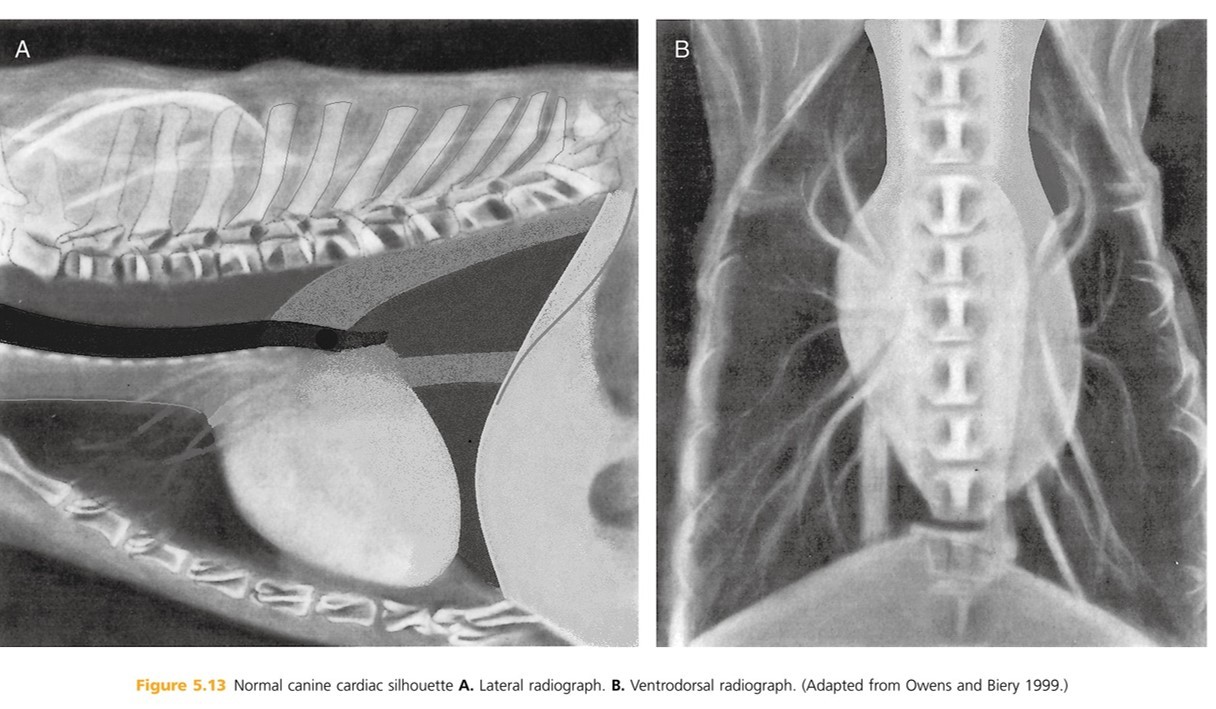

Heart: The shadow is actually the pericardium and the heart should be termed the cardiac silhouette. The cardiac silhouette fills about 3/4 of the thorax in a lateral view and 2/3 in a DV/VD view. Minimal heart enlargement will be hard to determine. The heart appears as a solid globe, so the boundaries are evaluated rather than the chambers. The cardiac silhouette should be less than half the width of the VD thorax at the level of the ninth rib.

The heart is obliquely positioned in thoracic cavity:

Lateral rad- long axis is approximately 45 degrees to perpendicular

Ventrodorsal rad- long axis is approximately 30 degrees to spine

The base of the heart is located at the ___ or ___ intercostal space. What does the heart base include? The tracheal bifurcation (coarina) is dorsal to base of the heart, approximately ____ % of the distance from sternum to spine.

5th or 6th

atria, ascending aorta, portions of pulmonary trunk, cranial vena cava

70%

The apex of the heart is formed by the _______ ______.

interventricular sepum

caudoventrally (back and down)

left